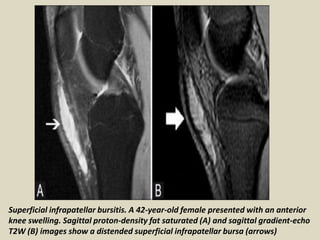

Superficial infrapatellar bursitis. A 42-year-old female presented with an anterior

knee swelling. Sagittal proton-density fat saturated (A) and sagittal gradient-echo

T2W (B) images show a distended superficial infrapatellar bursa (arrows)